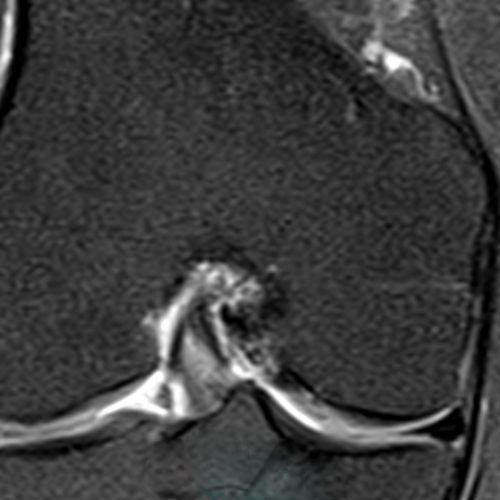

Lesão horizontal do menisco lateral e cisto parameniscal.

Corredora com dores na região do compartimento lateral do joelho e sensação de aumento de volume com formação de um nódulo palpável.

Realizado exame de ressonância magnética com identificação de lesão horizontal do menisco lateral (seta pequena) e formação cística parameniscal.